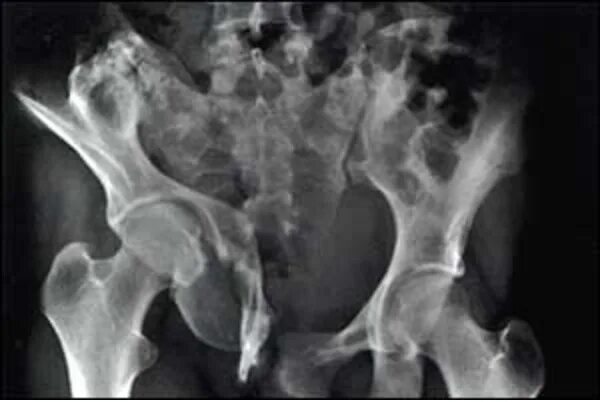

Анкилоз тазобедренного сустава